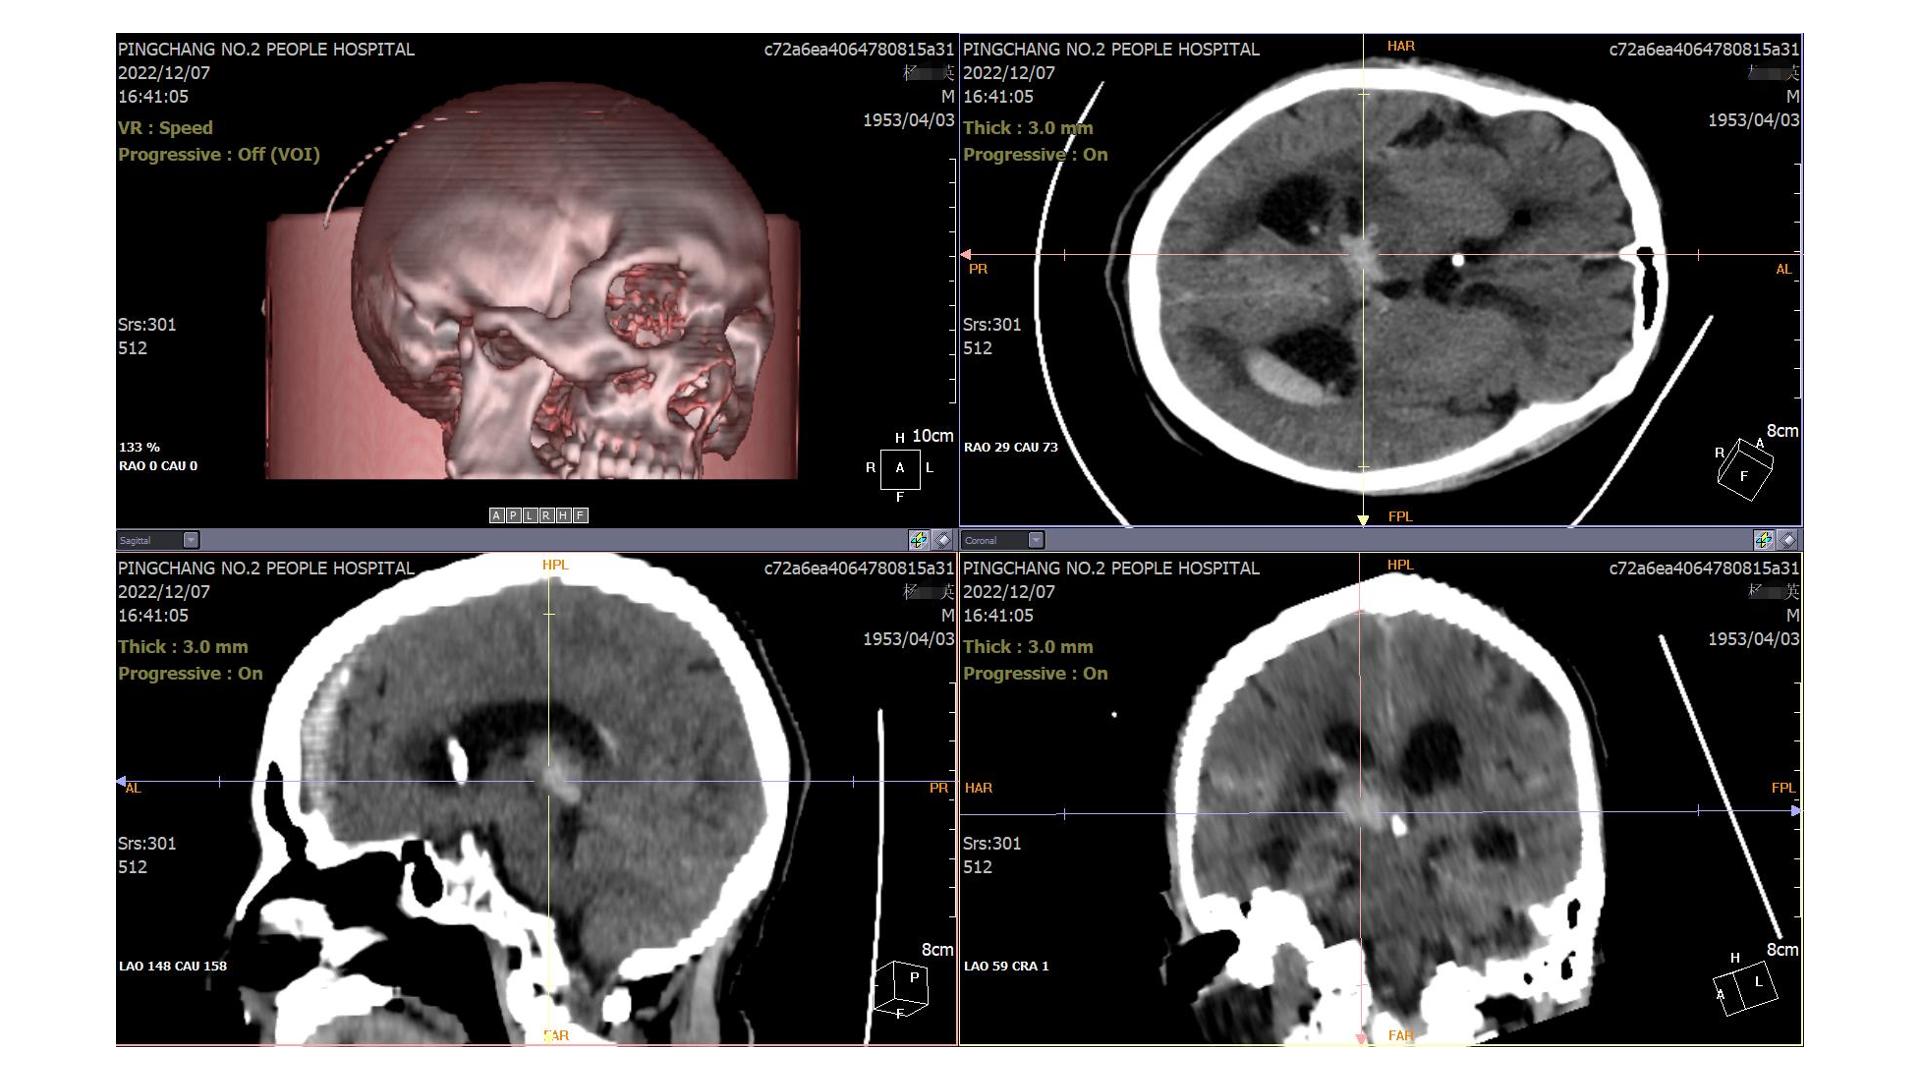

2022.12.07